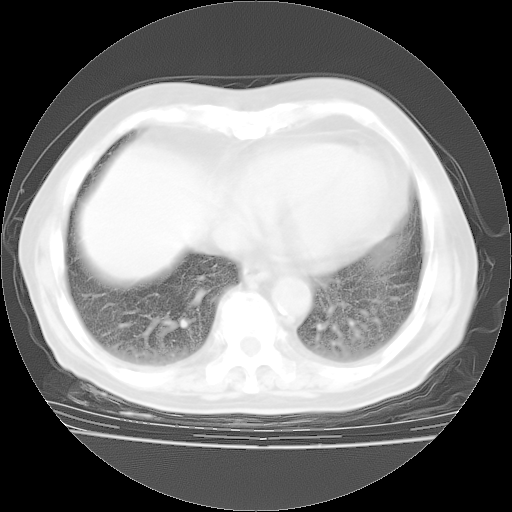

4月28日肺部CT——再次出现类似去年5月9日——透光度降低,“间质性”改变。

4月28日肺部CT——再次出现类似去年5月9日——磨玻璃样、间有“粟粒样”改变。

个人阅读4.14日肺部CT平扫:纵隔窗无异常,但肺窗示:双下肺内、后基底段有片絮状侵润影,部位以后基底段为著,以间质改变为主,呈急性肺泡炎征像,和首次住院影像学有相似之处。仅是个人读片,明日请相关专家再读片哈。其它建议同上。

1、108#的是4月14日的胸部CT(发此贴时还没看着28日的CT)。14日的胸部CT其实已经出现改变(如108#所述),个人认为28日的胸部CT除纵膈窗疑似有双侧胸膜增厚或少量胸积液(可行胸部B超明确)外,与4月14日对照病变有所加重;2、已经给予“异烟肼、利福平、乙胺丁醇”抗痨治疗?如果是,甲强龙80mg可缓慢减量;如果环磷酰胺已停用,暂不使用;3、中性粒细胞92%,明显升高,目前体温情况?注意合并细菌感染可能,使用左氧氟沙星情况下,是否联用B-内酰胺类抗菌药物?另外是查免疫全套非风湿全套。

今请临免主任会诊后认为:4月14日胸部CT已有双下肺间质性改变。患者病情复发多系激素减量过快不正规所致。目前甲强龙80mg/日,一周后酌情开始减量,不易过快。环磷酰胺若已停用,暂不使用。他同意目前抗菌药物使用,但应考虑是否加用B-内酰胺类抗菌药物(中性细胞明显增高);2、结核复发目前依据不足;3、若免疫全套各项指标正常,考虑多系特发性肺间质炎可能大。4、加强支持,并注意保护胃黏膜。

今上午去请教了临免、呼吸主任:1、介绍病史和阅读系列胸部CT一致认为:患者肺结核不考虑,仍为肺间质纤维化,目前处于急性肺泡炎阶段。2、若仍发热,可将甲强龙增至:80mg Bid静滴,同时鉴于中性增高,合并细菌感染可能,继续左氧氟沙星治疗,再联用B-内酰胺抗菌药物,如头孢哌酮--舒巴坦;3、停用抗痨药;4、目前甲强龙每日剂量160mg ,体温正常后再酌情减量;目前暂不用免疫抑制剂;4、不建议使用免疫增强剂等;5、加强支持治疗,鼓励患者进食;5、注意随访肝、肾功及血常规情况;6、因患者目前激素用量较大,加用胃黏膜保护剂,防止消化道出血可能。